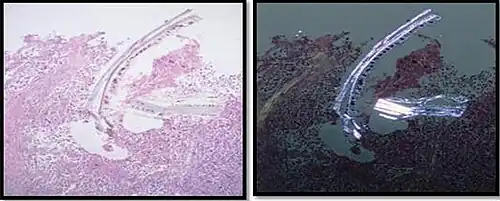

In microscopy, an artifact is an apparent structural detail that is caused by the processing of the specimen and is thus not a legitimate feature of the specimen. In light microscopy, artifacts may be produced by air bubbles trapped under the slide's cover slip.[1]

A crush artifact is an artificial elongation and distortion seen in histopathology and cytopathology studies, presumably because of iatrogenic compression of tissues. Distortion can be caused by the slightest compression of tissue and can provide difficulties in diagnosis.[2][3] It may cause chromatin to be squeezed out of nuclei.[4] Inflammatory and tumor cells are most susceptible to crush artifacts.[4]

- Crush artifact from compression by forceps on the tissue sample

- Air bubble entrapment artifact in a shoulder joint biopsy